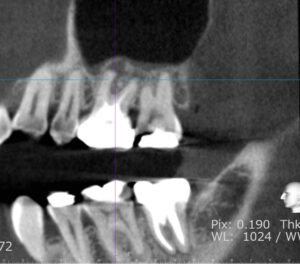

CTレントゲン検査を行いますのでその際、11000円かかります。